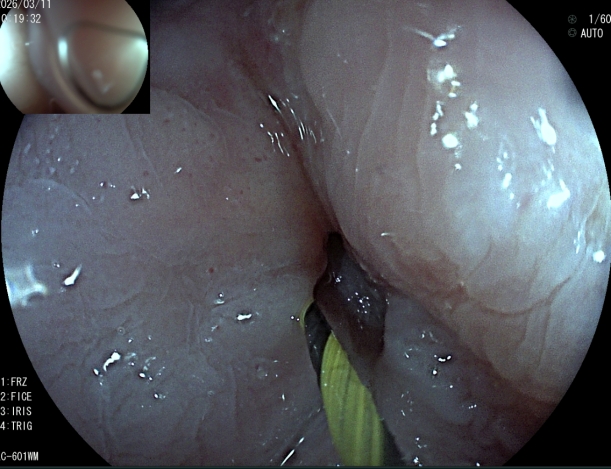

术前、术中、完成造瘘的食管

为破解这一临床难题,医院坚持守正创新,中西医并重。创新利用子镜直视探查+导丝精准引导+扩张+造瘘一体化的零射线术式。手术全程在高清直视下完成,术者能够清晰辨识狭窄通道与黏膜结构,安全引导导丝跨越闭塞段,同步完成食管扩张与经皮胃造瘘,三大技术无缝衔接,一次成型,全程零射线。创伤更小、恢复更快。